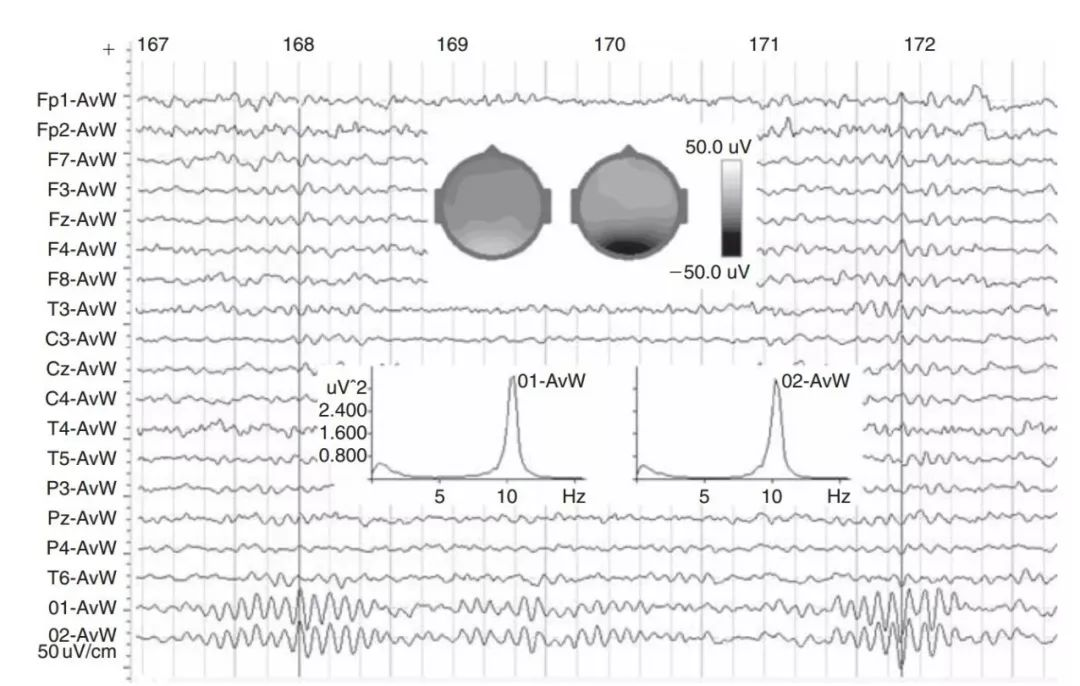

如图2所示,被试在睁眼状态下可以在O1和O2脑区观察到显著的alpha节律;被试O1和O2电极的alpha节律一般是同步化的,但是对于某些健康被试来说,O1和O2的alpha节律可能是相互独立的。此外,当被试闭眼清醒状态时,枕叶alpha节律会大幅度增强,如图3所示。

图2

图2